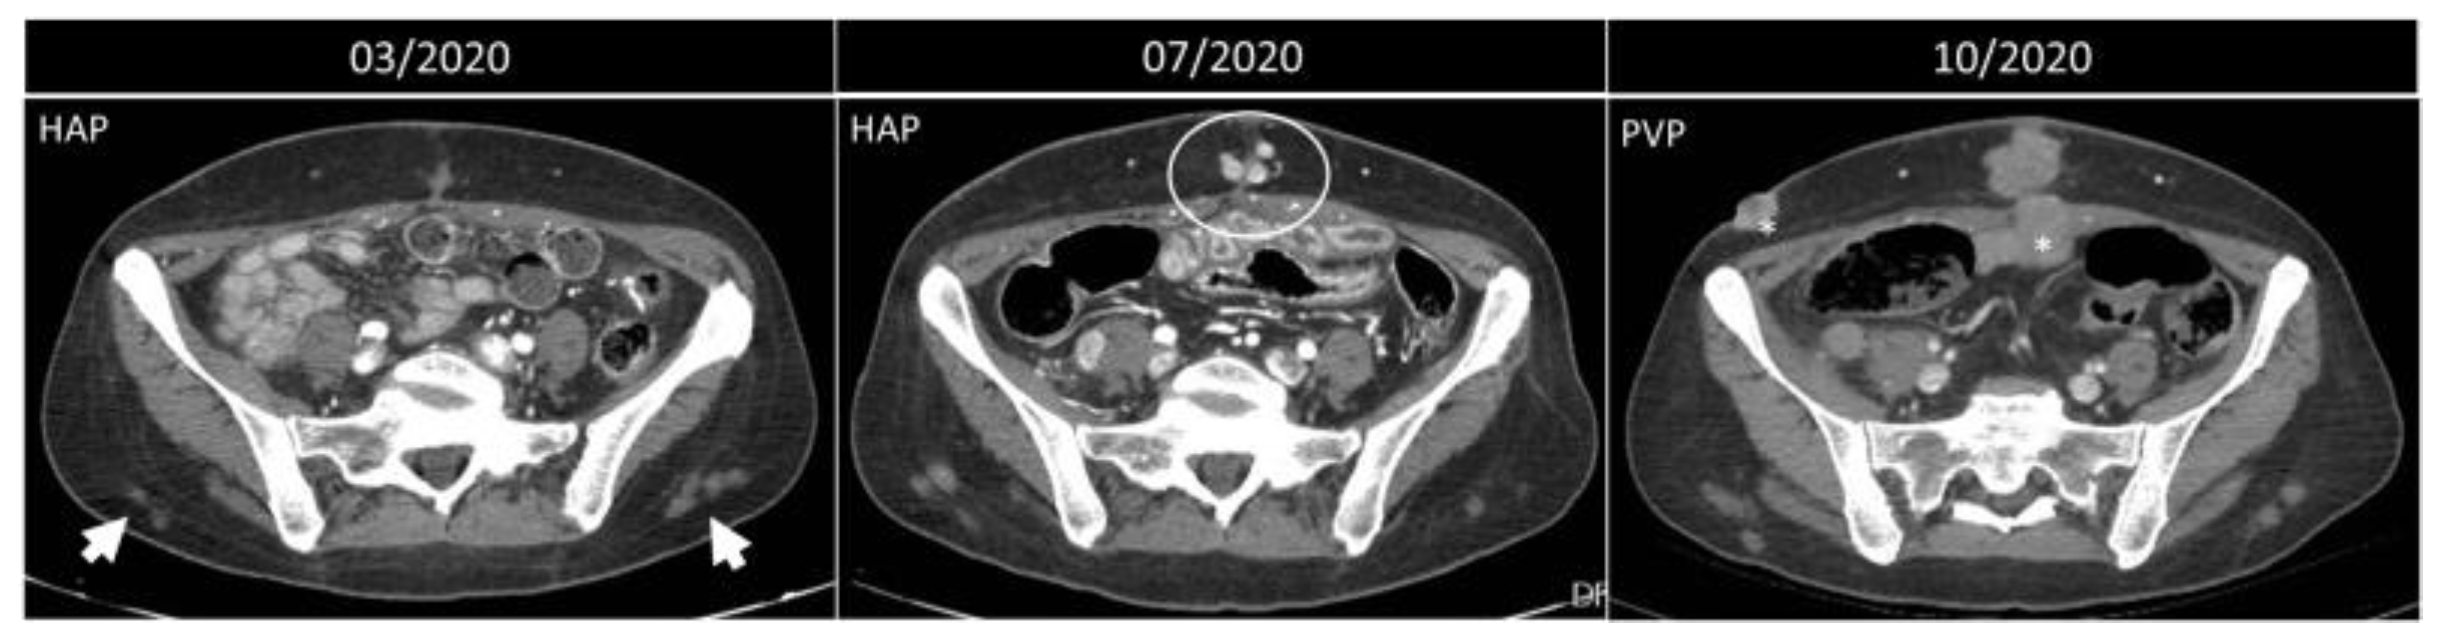

Figure 12. Progression of metastatic disease vs. injection granulomas. Axial, contrast-enhanced arterial and portal-phase CT scans of a 50-year-old woman with NEC of the small bowel. Three months after the surgery, some lesions on the subcutaneous fat of the lower back are noted (arrowheads). Four months later, these nodules are the same size, while along the surgical scar, new enhancing nodules appear (circle). In October 2020, these latter lesions become confluent and bigger, and other lesions appear (*), all compatible with metastatic nodules, while the nodules on the posterior abdominal wall are simple granulomas.